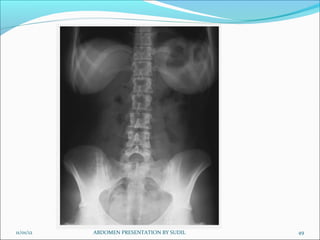

Picture criteria:

 Whole of abdomen from upper abdomen to symphysis pubis.

 Lateral abdominal wall and the properitoneal fat layer.

 Psoas muscle, lower border of liver and the kidneys.

 Ribs and spinous processes of the lumbar vertebra.

 Whole of the urinary tract should be visualized.

 Bowel gas pattern with minimal unsharpness.